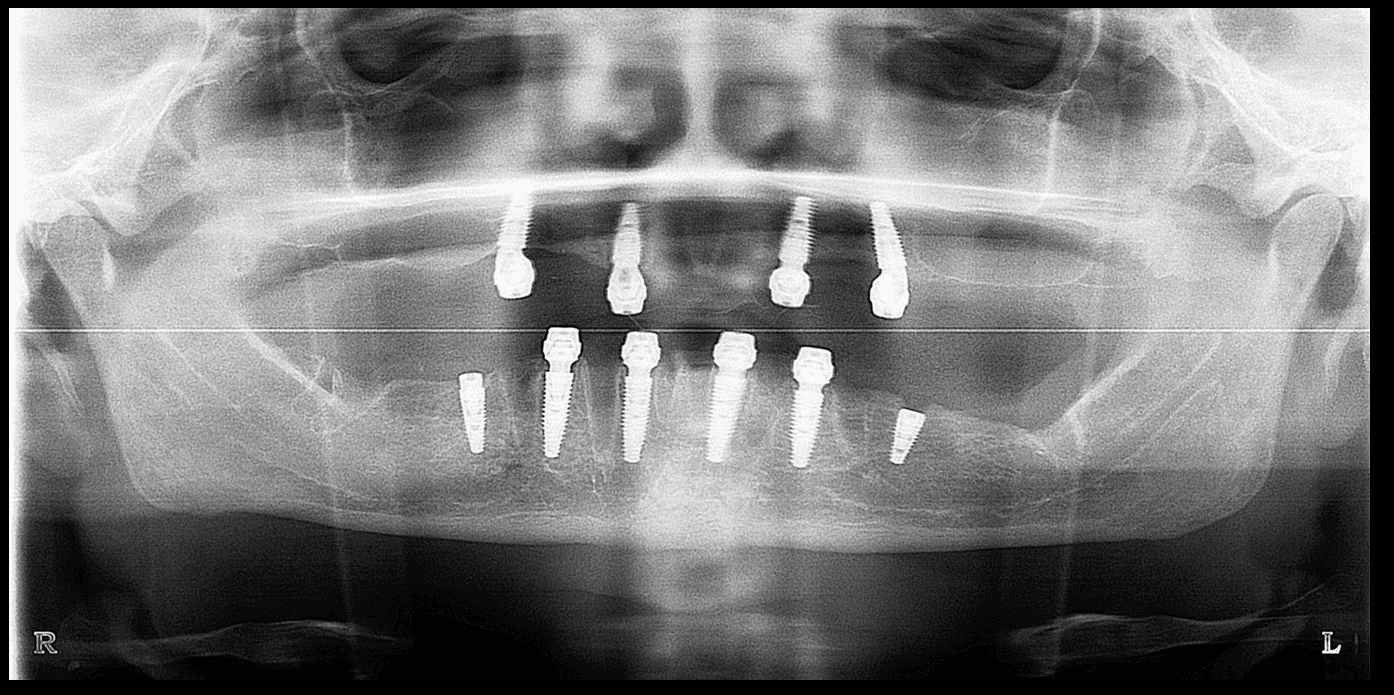

All on 6 Dental Implants Turkey

If you have multiple missing teeth in the mouth, our all on 6 dental implants in Turkey treatment option is the most suitable solution to replace all sets of teeth. All oral and maxillofacial implant procedures are safely performed by our specialist physicians who can replace all sets of teeth.